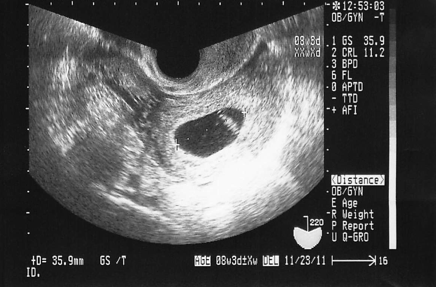

Aug , 17 · 妊娠7週目(7w0d~6d)のエコー写真とエピソード|妊娠2ヶ月 妊娠7週目は、妊娠2ヶ月の最終週でいわゆる妊娠初期にあたります。 ママのお腹はそこまで大きな見た目の変化はありませんが、赤ちゃんは魚のようだった形から人の形へ、大きさは1センチ弱へと変化していく段階です。Jul 17, · 妊娠7週目の超音波(エコー)写真。 赤ちゃんの大きさや成長は? 妊娠7週目の赤ちゃんは「胎芽」と呼ばれる最後の週で、大きさは 「頭殿長(CRL):9~14mm、胎嚢(GS):25mm~45mm」May 23, 18 · 妊娠12週~16週になると、お腹の赤ちゃんが大きくなり過ぎて、経膣エコーでは撮影が難しくなります。 そのためそれ以降は子宮付近からではなくお腹の外、遠くから撮影する腹部エコーへと切り替わります。

受精から21~27日目 胎芽(胎児)の大きさ 頭殿長(座高)が2mm足らず 妊娠5週(5w)は、まだ超音波検査では心拍が確認できない週数ですが、赤ちゃんは内胚葉・中胚葉・外肺葉と3つの細胞のグループにわかれて発達してゆきます。 そのうちの1つ、心臓や血液、骨、筋肉を作る中間グループ (中胚葉)の細胞は、赤ちゃんの栄養が蓄えられている卵黄のうと妊娠週5w3d 7月に着床しきれず科学流産してました(´°̥̥̥̥̥̥̥̥ω°̥̥̥̥̥̥̥̥`) 11月19日陽性反応でて 5w4dに初診しに行きました! おー!Jan 28, 19 · 心拍が確認できる 妊娠7週目のエコー写真 D=103mm 心拍が確認できる 心拍が初めて確認できました。この2週間、正直流産の不安の方が大きくて、「ちゃんとおなかの中で元気かな? 」と心配ばかり。

Mar 05, 15 · 妊娠7週は妊娠2ヶ月の第4週にあたります。 この時期の赤ちゃんは胎児ではなく胎芽(たいが)と呼ばれます。 それまであったエラやしっぽがなくなり、重要な器官が作られる「器官形成期」が終盤を迎えるころです。 まだ2頭身で性別による見た目の違いもありませんが、着実に人間らしい姿に近づいていますよ。 エコー検査では胎嚢(たいのう)という袋の中に